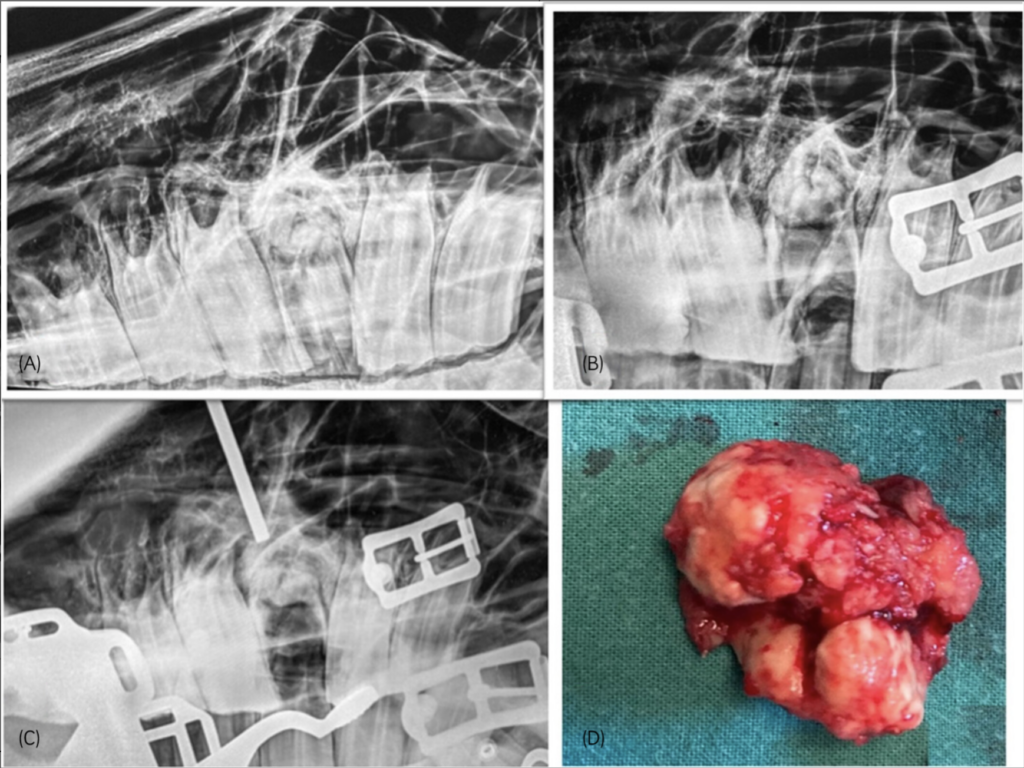

Researchers reviewed clinical records of horses that underwent cheek tooth repulsion (2014-2023). Inclusion criteria were: mandibular or maxillary cheek tooth extraction where oral extraction failed and repulsion was used to complete extraction and where clinical follow-up information was available. Repulsions were carried out under sedation with a regional nerve block or under a short general anesthetic using a small diameter repulsion pin (3-5 mm). Intraoperative radiographs facilitated instrument placement. The alveolus was packed with polymethyl methacrylate post-extraction. Horses were reexamined four to six weeks postoperatively.

The study included 20 cases. Patients had a mean age of 10.3 years (range 5-16 years). The majority (75%) of teeth had preexisting dental fractures. Maxillary (n = 15) and mandibular cheek teeth (n = 5) were all successfully repulsed, with 16 cases performed with the horse standing and four with the horse under general anesthesia. Intraoperative complications included damage to the mandibular bone (n = 1). Short-term complications (n = 2) included superficial surgical site infection and dehiscence of one sinus flap. Long-term complications included the recurrence of sinusitis (n = 1) and small intra-alveolar fragments causing persistent bitting problems in another patient.